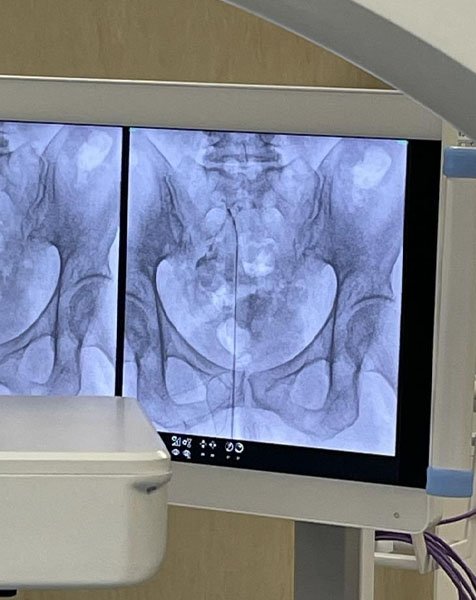

Alcune foto del nostro trattamento di epidurolisi.